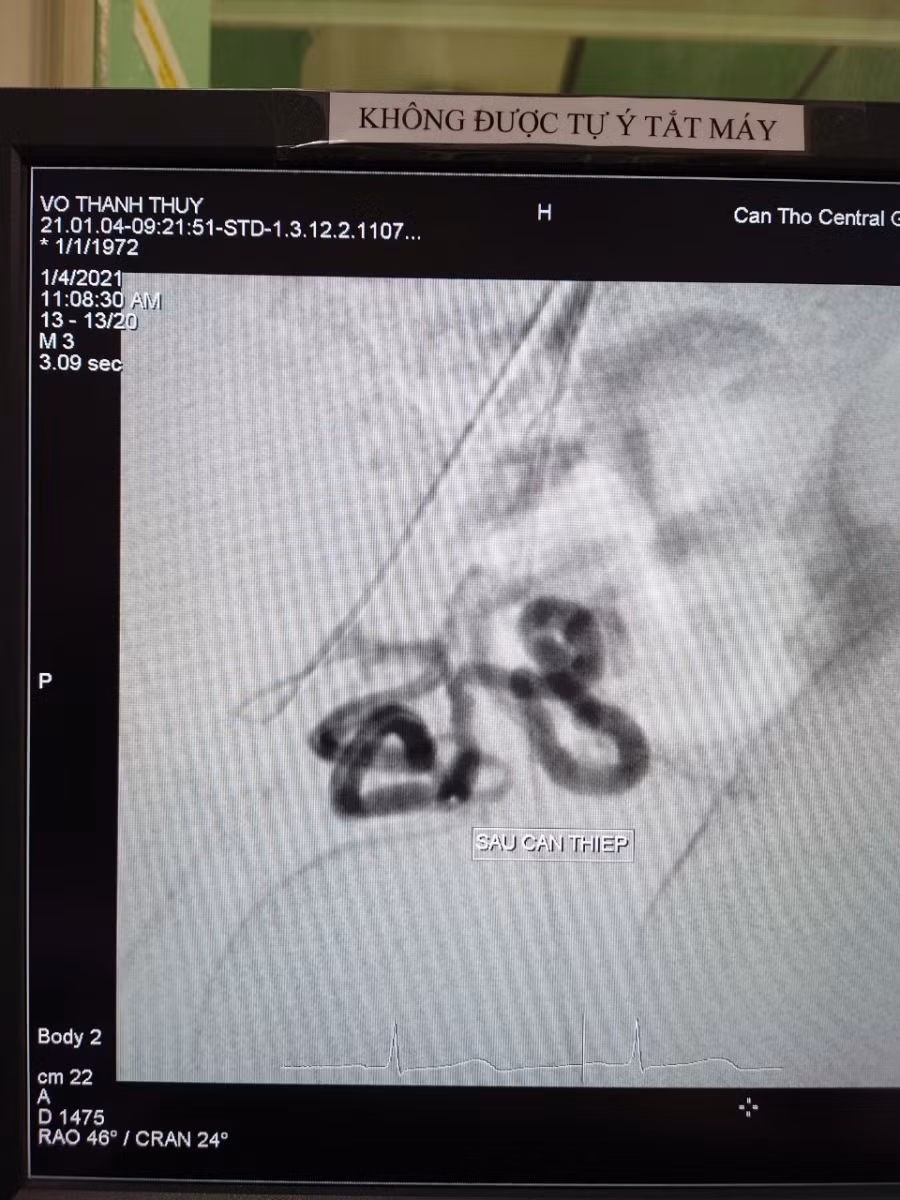

Trước tình huống này, qua hội chẩn liên khoa, các bác sĩ xác định chẩn đoán: U xơ tử cung biến chứng xuất huyết tiến triển/huyết khối tĩnh mạch sâu chi dưới lan rộng. Cùng lúc các bác sĩ phải giải quyết tình trạng rong huyết và điều trị tình trạng huyết khối tĩnh mạch sâu chi dưới.

Theo Bs.CKI Trần Công Khánh, điều trị tắc mạch có chỉ định khi u xơ tử cung gây đau bụng, rong kinh rong huyết, rối loạn tiểu tiện đại tiện…; kích thước u < 10cm (khuyến cáo) và bệnh nhân không muốn phẫu thuật. Nếu bệnh nhân chưa có con cần thảo luận với bác sĩ sản khoa trong việc lựa chọn nút động mạch tử cung hay phẫu thuật nội soi bóc nhân xơ.